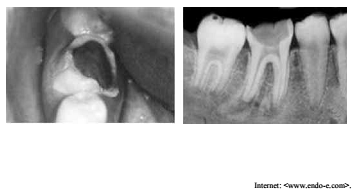

As imagens precedentes referem-se a um paciente com

quatorze anos de idade que procurou atendimento odontológico,

queixando-se da presença de uma gengiva no meio de um dente do

lado direito.

Considerando as imagens apresentadas, assinale a opção correta.

A gengiva no meio do dente, a qual o paciente se referiu, é o

tecido conjuntivo da alteração pulpar, que tem características

gerais de tecidos inflamados em fase aguda, com

predominância de linfócitos, plasmócitos e macrófagos

associados a fibroblastos e vasos sanguíneos neoformados,

além de mastócitos.

Nesse tipo de lesão, a neoformação vascular proporciona um

rico suplemento sanguíneo e possibilita uma resistência a

infecções quando associada à defesa do indivíduo jovem. Essa

situação pode justificar o fato de a polpa jovem não sofrer

necrose após uma exposição, mas sofrer hiperplasia.

Essa forma aguda de inflamação pulpar, provocada pela cárie,

produziu um tecido de granulação hiperplásico que invade a

câmara pulpar, preenchendo toda a cavidade cariosa.

Além da possível sensação de pressão durante a mastigação,

esse pólipo pulpar possui, em geral, sintomatologia dolorosa

espontânea, severa, contínua, exacerbada em posição

horizontal.